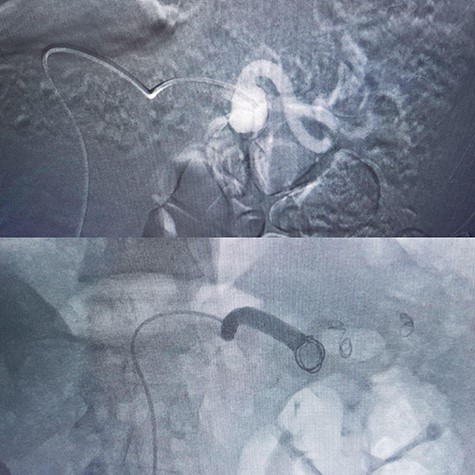

5 | Male | 52 | 6 cm | Hybrid surgery (proximal control by balloon + aneurysm resection (Fig. 4) | Proximal | Discharged |

In a 52-year-old man (third patient), 3-cm SAA was found incidentally in ultrasound and CTA. According to size of the aneurysm, he was candidate for endovascular treatment. Angiography and positioning of the coils on either side of the aneurysm (‘sandwich technique’) was completed (Fig. 3). Post-embolization checks were performed with selective splenic, celiac and superior mesenteric artery angiograms to confirm occlusion of the main splenic artery and patency of the collateral arteries. All seven patients discharged with no procedure-related complications.

There are two embolization techniques: endovascular ligation that requires the positioning of the coils on either side of the aneurysm (‘sandwich technique’) to attain complete occlusion. For patients with large or multiple SAAs, total embolization of the splenic artery must be performed to produce complete occlusion of the SAAs [9]. In cases 4 and 5 we started EVT but as they were giant aneurysms we continued by laparotomy (the hybrid surgery).